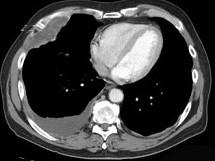

70岁,男,以前是管道安装工,有石棉接触史,也有很长的吸烟史,请结合CT检查选出最可能的诊断 ( ) HX-2864.jpg

• A.胸膜间皮瘤

• B.神经鞘瘤

• C.胸膜肥厚

• D.淋巴瘤

• E.石棉肺